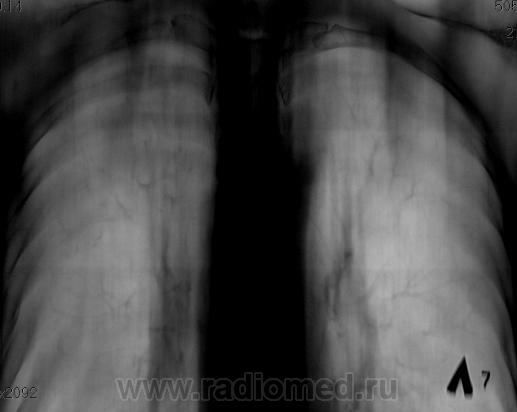

По томограммам не понятно что хотели получить? Интересовали эти маленькие плотные очаги?

Справа на верхушке инфильтративная тень. Слева в задних отделах мелкие буллы.

На последнем срезе тень в 1 сегменте, мелкие полости в верхних долях с обеих сторон.